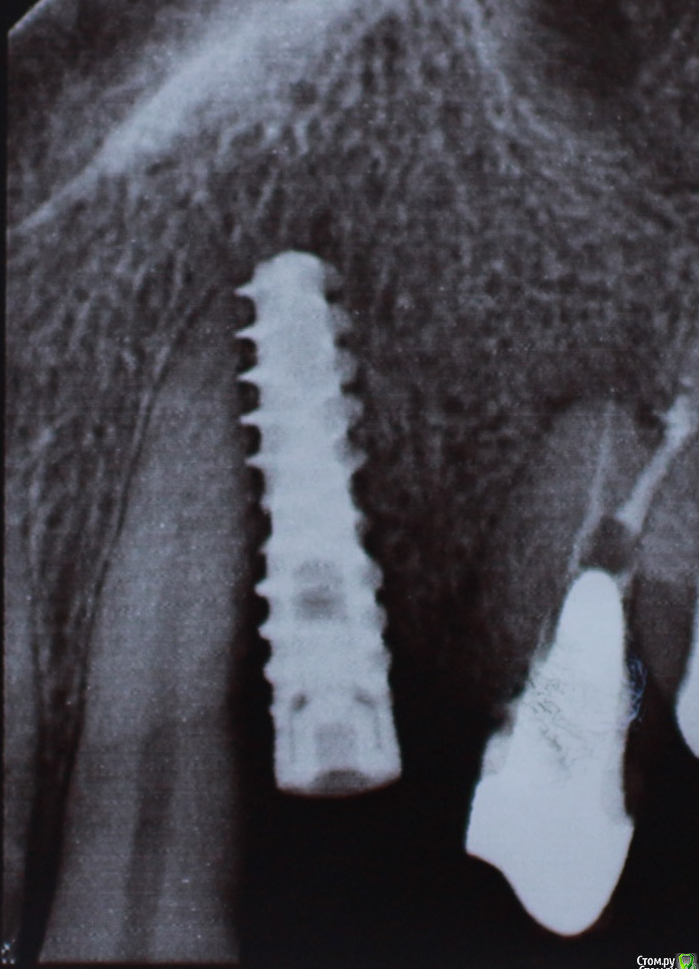

alex_ddd Опубликовано 29 июля, 2016 Автор Поделиться Опубликовано 29 июля, 2016 Ну, вот сегодняшний снимок 24 Ссылка на комментарий

alex_ddd Опубликовано 29 июля, 2016 Автор Поделиться Опубликовано 29 июля, 2016 Попытка 2 Ссылка на комментарий